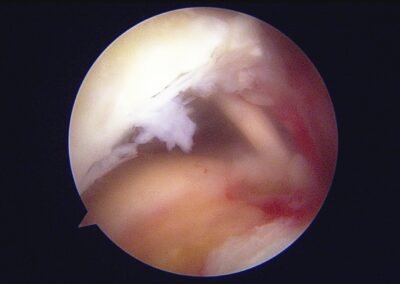

GalleryShoulder rotator cuff repair Meniscus root repair Meniscus repair Bankart repair for recurrent shoulder dislocation ACL reconstruction Machines Instruments